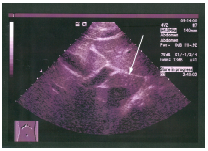

69 一病人主訴右上腹部疼痛,其右腎超音波之長軸切面如圖示,下列敘述何者正確?

(A) 腎臟先天性異常,可能具有雙套集尿系統 (B) 先天性血管異常(C) 腎惡性腫瘤 (D) 馬蹄腎